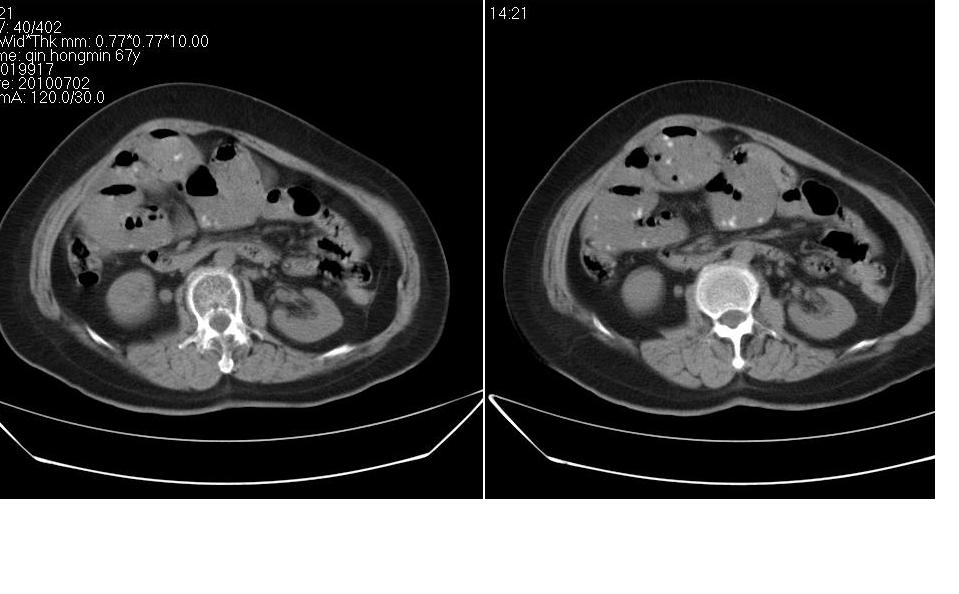

女 67岁,以腹疼就诊,不发热,八年前有肠梗阻病史,炎热的夏天,下午又吃了两块西瓜及两个桃子,以后无大便,不放屁。

右侧腹部膨隆左侧塌陷,小肠积气积液扩张,肠袢迂曲扭转,远侧肠曲无异常,考虑高位肠梗阻,小肠扭转可能,具体可能为3、4组,建议扫描全腹。此外胆囊大。先对症保守治疗,必要时手术。

腹内疝很罕见的,此处可发生盲肠旁疝但不符。那个是粪石??